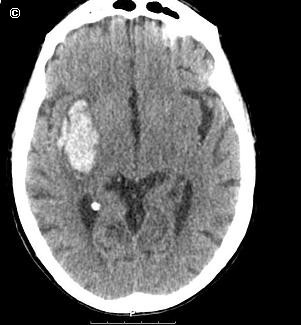

Acidente Vascular Cerebral Hemorrágico

O que é? O acidente vascular cerebral hemorrágico (AVCH) se caracteriza pelo sangramento em uma [...]